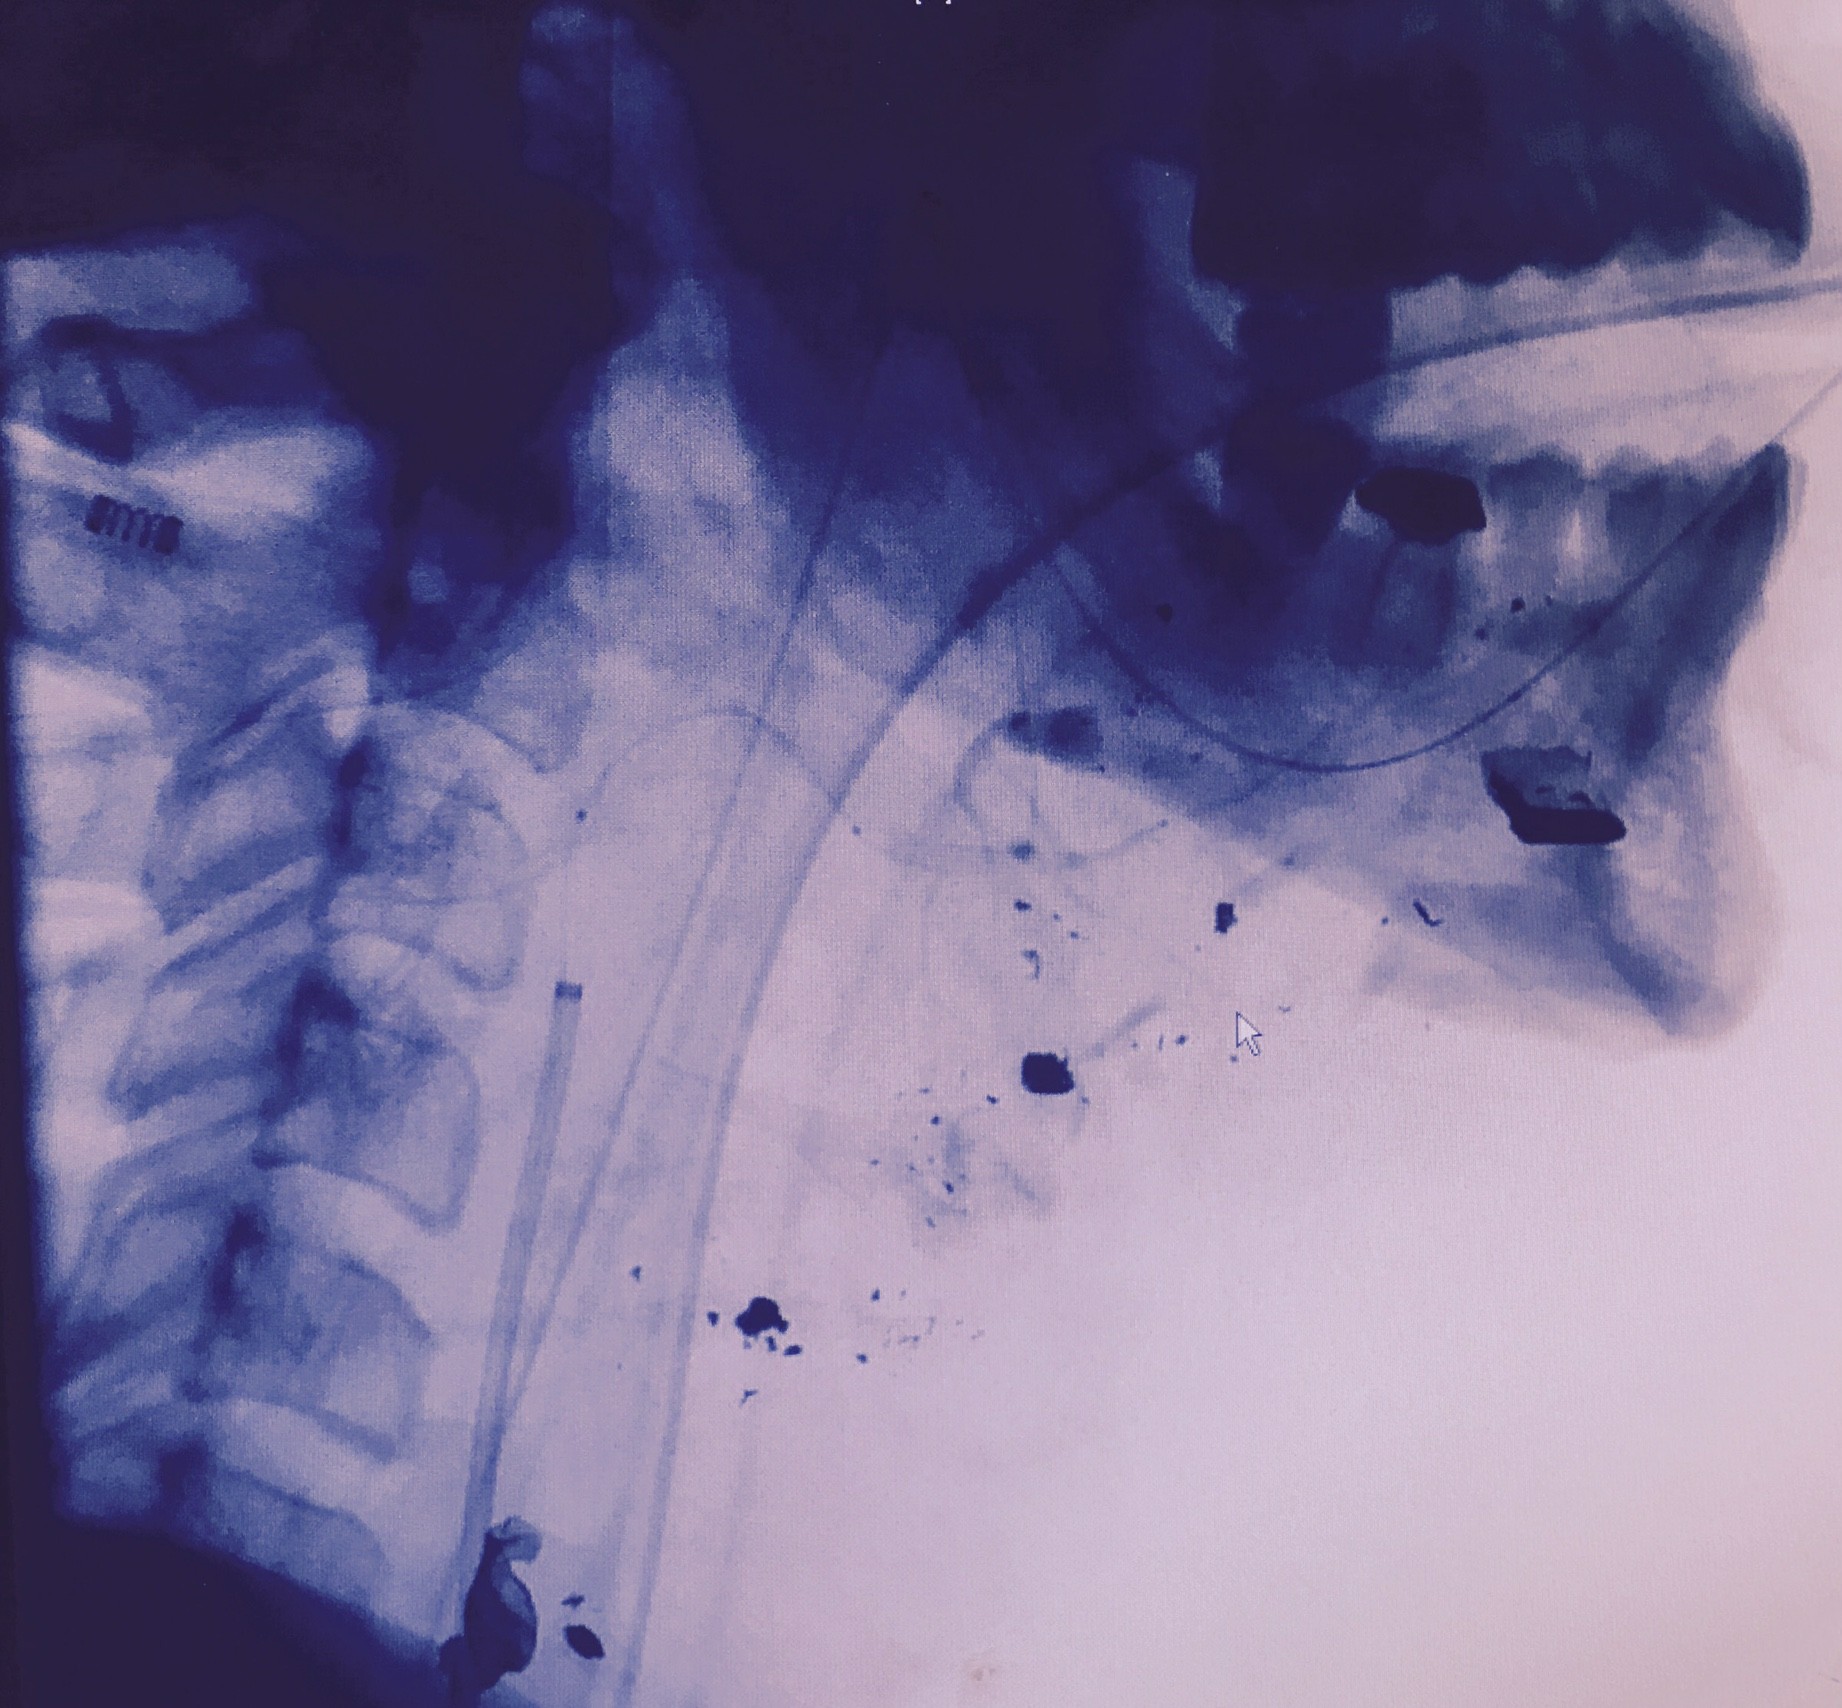

I guess you can say my entrepreneurial journey began after my greatest risk. In January 2016 I found myself laying face down in a pool of my own blood after a federal fugitive on the run decided to shoot me in the face while I slept and held my girlfriend hostage as I bled out, dying. By the gift of the gods, my father’s dedication to not letting the surgeons give up on me and the absolutely amazing doctors and nurses at KU med, my life was saved when the odds were 100% stacked against me.

I was told I would never be able to use my hand again due to nerve damage to my spine… not to mention was bound for a life of opioid management to deal with the pain. I was absolutely lost with how my life would look moving forward. My lady is from Iowa and suggested we move there to begin a new journey. I arrived in Des Moines with barely enough money to even put down a deposit on a small apartment. I had no idea what to do and had no leads on a job. I knew working for myself was the only option. I took up side gigs from graphic design to videography. I hustled daily to put money away so I can build my own company. At the time anything Cannabis related was illegal in Iowa, but cannabis had been such a huge part of my life and especially my healing. I was able to get off of the opioids I was prescribed with the help of cannabis. It truly was life changing and I wanted to give that gift back to those around me.